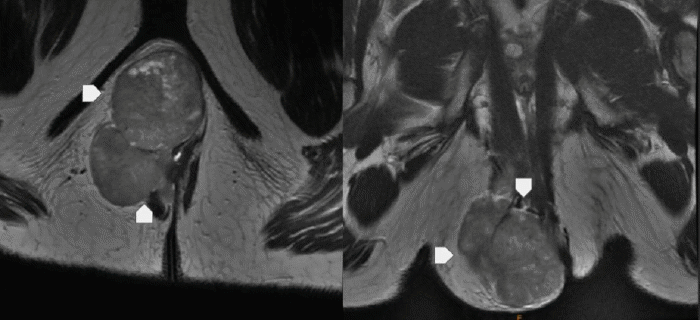

Initial workup, initiated by the patient’s primary care physician four months prior to presentation, included a CT scan of the abdomen and pelvis. This study identified a 7.5 × 4.4 × 9.8 cm lobulated soft tissue mass exhibiting heterogeneous density within the right ischiorectal fossa. Subsequent MRI of the pelvis provided further characterization, demonstrating a multilobulated, smoothly marginated, enhancing mass arising appearing to arise from the undersurface of the pelvic floor and extending inferiorly through the right ischiorectal fossa (Figure 1). There was no obvious invasion into the adjacent anorectal structures or involvement of pelvic osseous structures, and no significant lymphadenopathy was noted. Anoscopy and colonoscopy were performed, confirming normal anorectal mucosa throughout without evidence of intraluminal lesions.

Figure 1. MRI of Ischiorectal Fossa Angioleiomyoma. Published with Permission

T2-weighted MRI of the pelvis. (A) Axial and (B) Coronal views demonstrating a large, well-circumscribed, encapsulated mass within the right ischiorectal fossa. The mass exerts significant mass effect, displacing the anorectal structures medially, but shows no definitive evidence of local invasion into adjacent muscle or bone